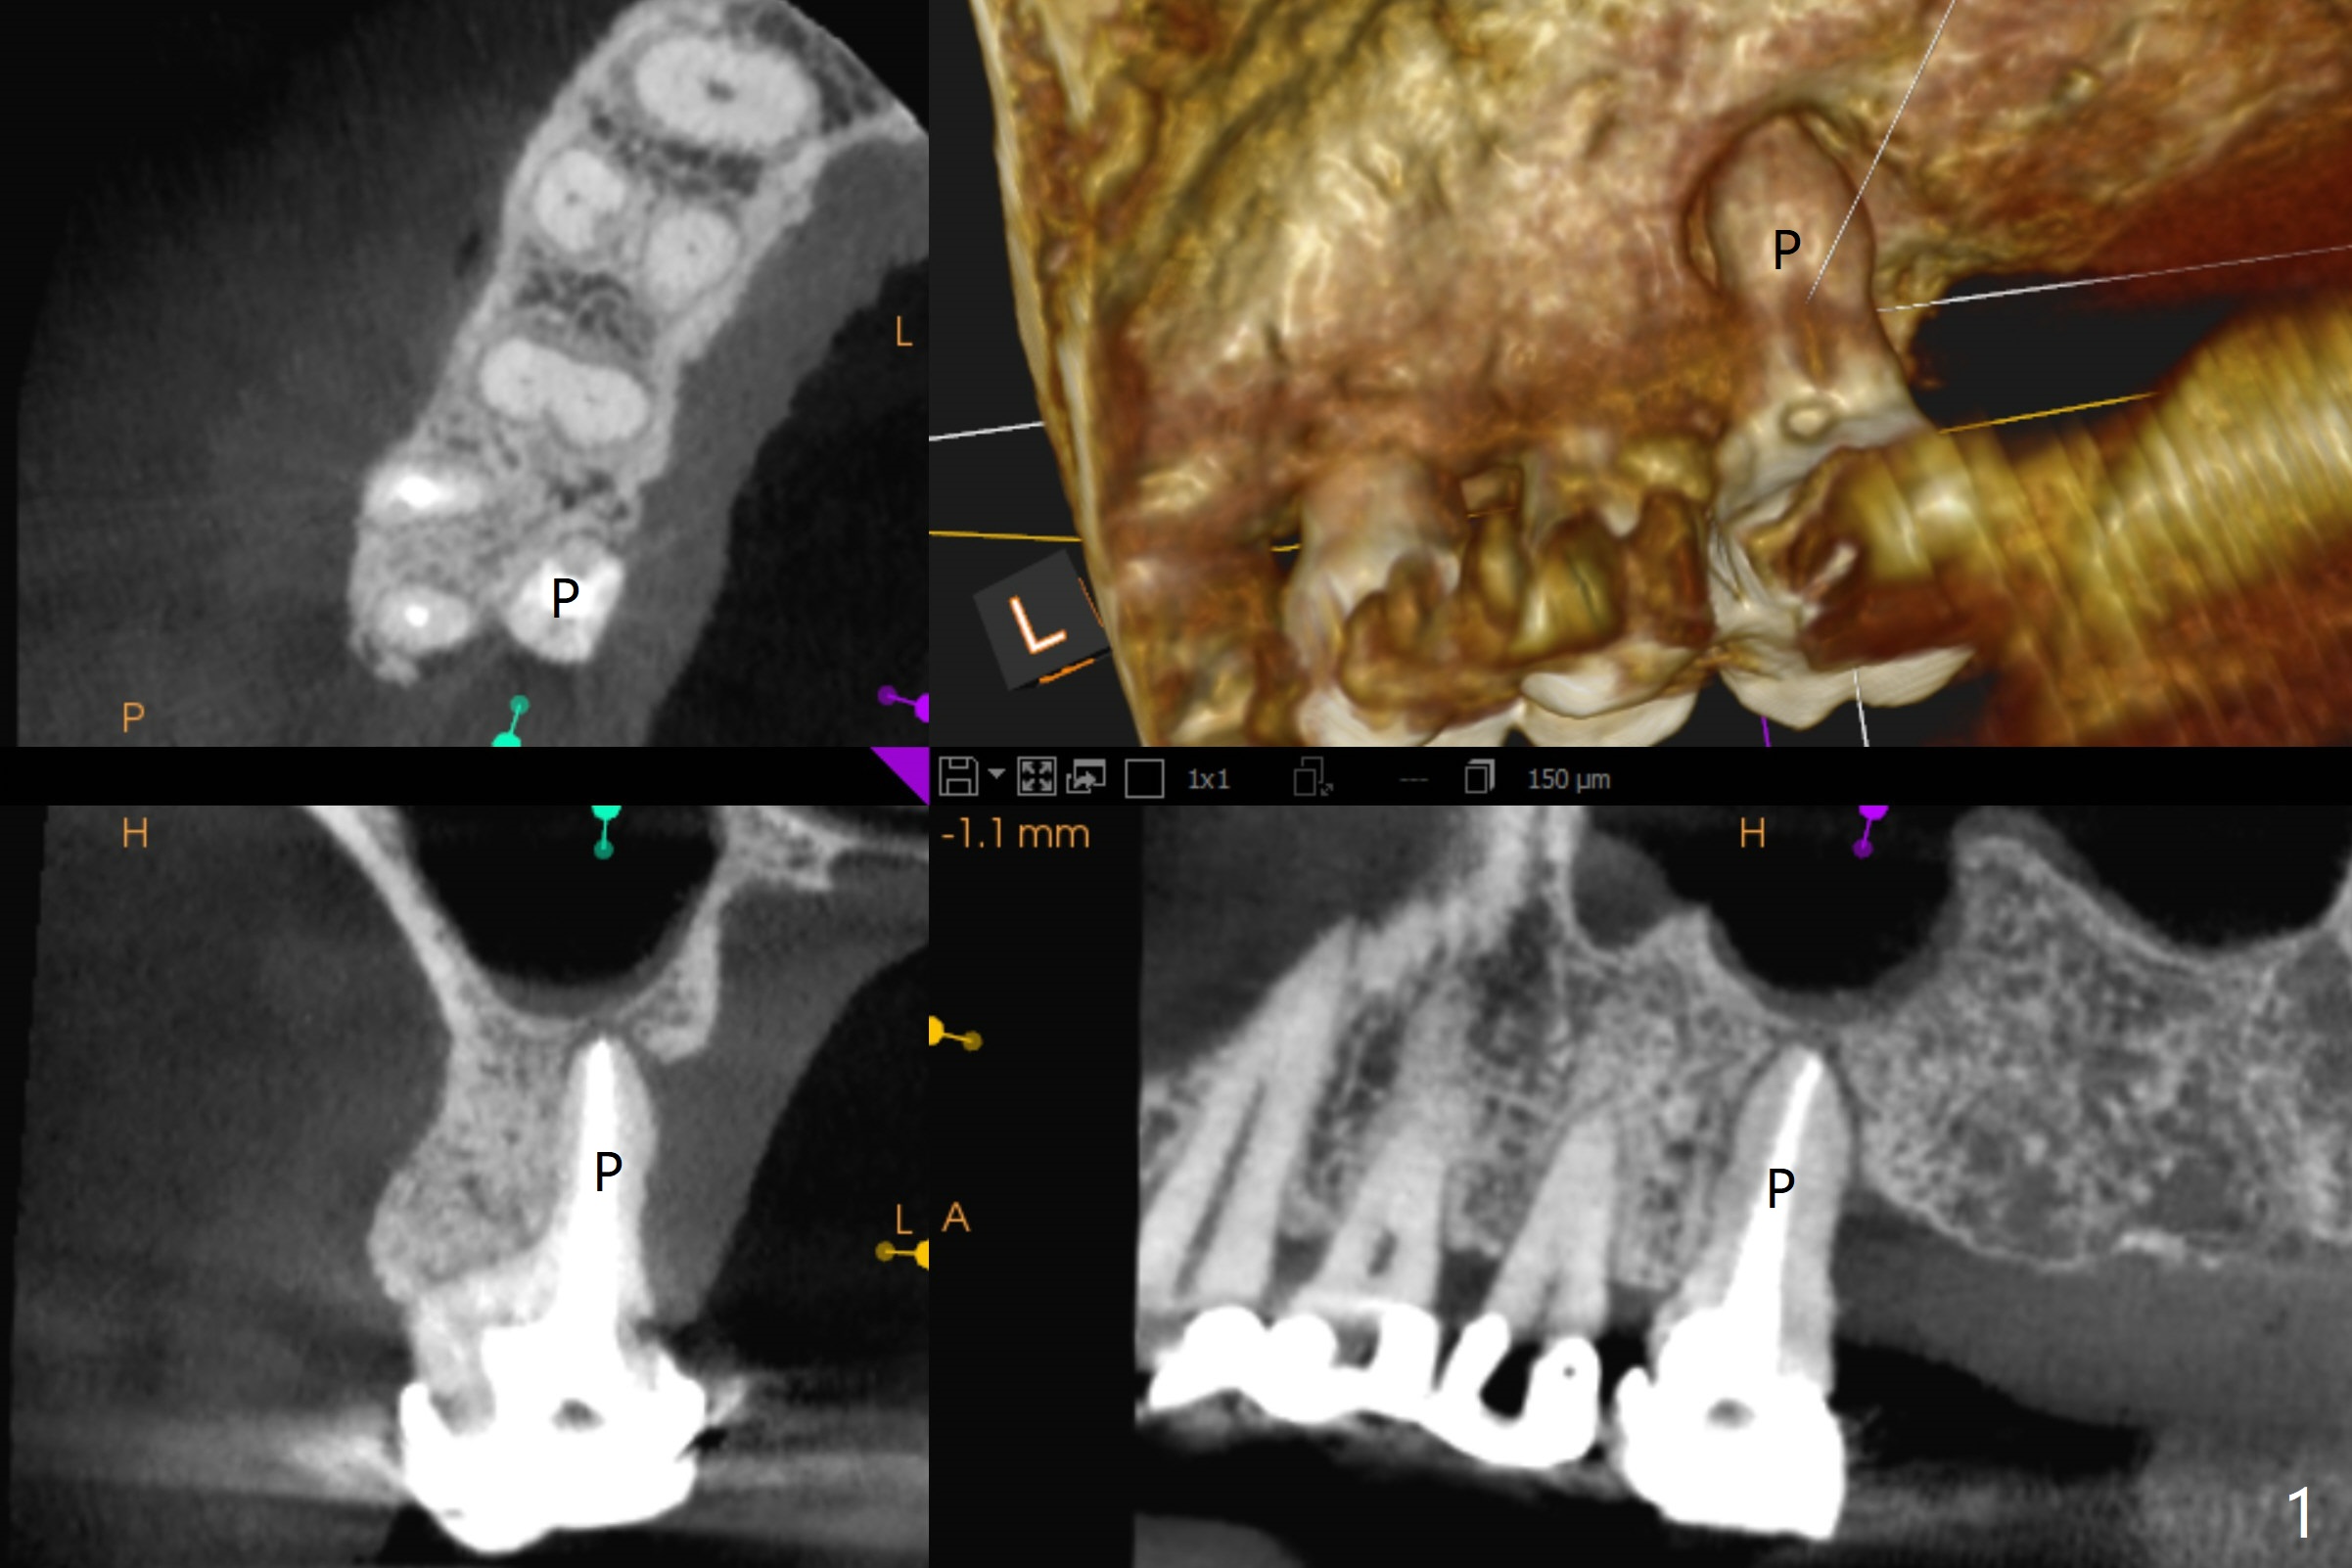

A 52-year-old woman has had chronic abscess associated with the tooth #3. The palatal root is exposed (Fig.1 P), suggesting root fracture. The apex of the mesiobuccal root seems to stick out of the buccal plate (Fig.2 *). The root canal filling is incomplete in the distobuccal root (Fig.3 *). The tooth appears to have guarded prognosis. Extraction and immediate implant is apparently a better option (Fig.4,5). It would be safer to start osteotomy in the middle of the remaining septum (Fig.6, as compared to Fig.5). After sinus lift with PRF membrane (Fig.7 yellow curved line) and implant placement (green), another piece of PRF membrane will be placed against the palatal wall of the socket, followed by bone graft (red circles) and a 25-degree angled abutment (pink).